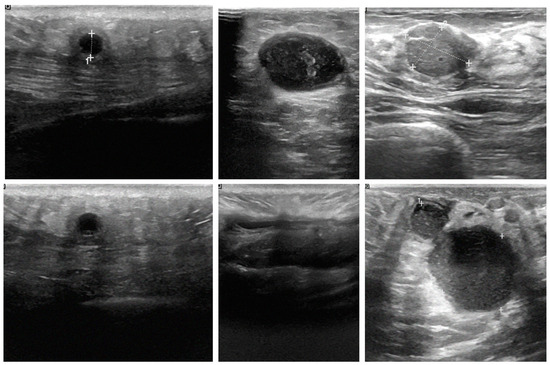

4.3. The Role of Cross-Modality Imaging

A key contribution of this study is the successful integration of cross-modality imaging, which combines mammography and ultrasound images, to enhance classification accuracy. By fusing features from these different imaging modalities, the models were able to leverage the complementary strengths of each, resulting in more robust and accurate classifications. For example, mammography excels at visualizing dense structures, while ultrasound provides detailed images of soft tissues. This integration allowed the AI models to perform more comprehensive analysis of breast tissue, which is crucial for accurate tumor detection. Ultrasound images, as shown in Figure 9A–C, depict various breast tissue characteristics, while mammography images, as shown in Figure 9D–F, illustrate different breast tissue densities. These images were instrumental in training and testing the AI models for breast cancer detection and classification.

Figure 9.

Comparison of breast tissue textures in sonography and mammography images.

The findings suggest that cross-modality imaging can significantly enhance AI-driven diagnostic tools, making them more reliable and versatile in different clinical scenarios. This approach is particularly beneficial in cases where a single imaging modality may not provide sufficient information for an accurate diagnosis. The ability to combine and analyze data from multiple sources could lead to earlier detection and better treatment outcomes for patients with breast cancer.